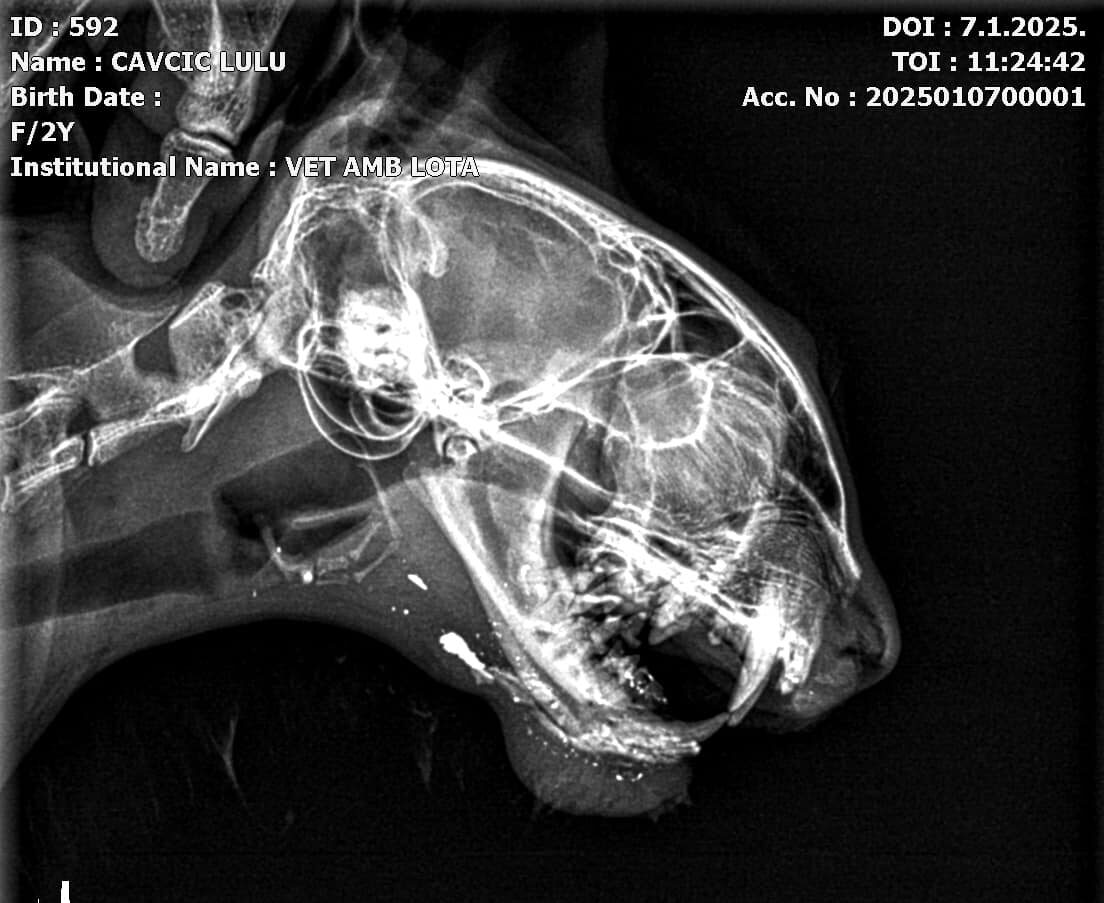

U ulici Lucije Rudan u Hvaru dogodio se novi slučaj brutalnog zlostavljanja životinje. Mlada ulična maca, poznata mještanima kao Lulu, pronađena je u teškom stanju nakon što se više od tjedan dana nije pojavljivala na svojoj uobičajenoj lokaciji. Lulu, koja ima osobu koja brine o njoj, vratila se kući izgledajući iscrpljeno i povrijeđeno. Nakon liječničkih pregleda, rendgenska snimka je pokazala da je bila upucana iz zračne puške, a metak je završio u njezinoj vilici. Lulu je trenutno u procesu oporavka, a slijedi operacija koja će joj omogućiti da preživi.

– Tko nas prati mogao je primjetiti da smo nekoliko dana bili u potrazi za našom Lulu, mladom uličnom macom koja ima osobu koja se o njoj brine. Lulu na svoju lokaciju nije dolazila vise od 7 dana, sto nas je zabrinulo. Kad se napokon vratila izgledala je jako loše i iscrpljeno. Rendgenska snimka je pokazala da ju je netko upucao iz zračne puške, te se metak nalazi u vilici. Slijedi operacija.